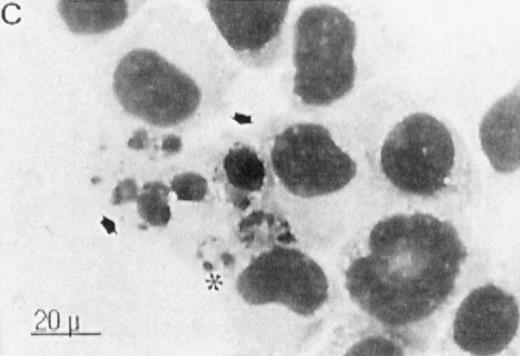

Several studies have suggested a role for TGase II in apoptosis.8-10 To examine whether the atRA-induced TGase II expression in RPMI 8226 cells was correlated with the induction of apoptosis, we performed both indirect immunofluorescence detection of TGase II protein (Fig 7, left panel) and MGG staining (Fig 7, right panel) of cells within 6 days of addition of different retinoids to the culture . Apoptosis was quantified by counting apoptotic cells after MGG and Hoechst 33258 staining. Count of TUNEL-positive cells gave similar results (Fig 8).

Correlation between the induction of TGase II protein and apoptosis in RPMI 8226 cells. Cells were incubated for 6 days in the absence of retinoids (A) or in the presence of 10−7 mol/LatRA (B) or the combination of both 10−7 mol/L CD367 and 10−7 mol/L CD2425 (C). TGase II protein expression was detected by indirect immunofluorescence using a monoclonal anti-TGase II antibody (left panel), and apoptotic cells were detected after MGG coloration on cytospin preparations (right panel).

As shown in Fig 7A, after treatment of RPMI 8226 cells with 10−7 mol/L CD367 or 10−7 mol/L CD2425 alone, neither apoptotic cell death (right panel) nor TGase II (left panel) were induced. The apoptotic index in the CD367- or CD2425-treated cultures was not different from that in control (Fig 8). Thus, mere activation of endogenous RARs by a RAR-selective retinoid such as CD367 or of endogenous RXRs by a RXR-selective retinoid such as CD2425 is insufficient to induce apoptosis in RPMI 8226 cells.

Interestingly, treatment with 10−7 mol/LatRA, the natural panagonist ligand, resulted in both TGase II induction (Fig 7B, left panel) and significant apoptosis. As shown in Fig 7B (right panel), numerous cells displayed the characteristics of a classical apoptotic phenotype with condensed nuclei, extensive cytoplasmic blebs, marked decrease in cellular volume, and cellular fragmentation. The apoptotic index of atRA-treated cells was approximately 12% (Fig 8). Finally, after 6 days of culture in the presence of both 10−7 mol/L CD367 and 10−7 mol/L CD2425, we observed the same morphological evidence of apoptosis as in atRA-treated cells (Fig 7C, right panel). The apoptotic index was in the 18% range (Fig 8). AfteratRA treatment TGase II appeared induced in cells undergoing apoptosis and accumulated in apoptotic bodies (Fig 7C, left panel). Taken together, our results showed that the induction of TGase II and apoptosis by retinoids in RPMI 8226 cells is linked and that the activation of both RARs and RXRs is required for the induction of apoptosis. Interestingly, the same requirement was observed for the inhibition of cell proliferation elicited by retinoids in RPMI 8226 cells (Fig 9).